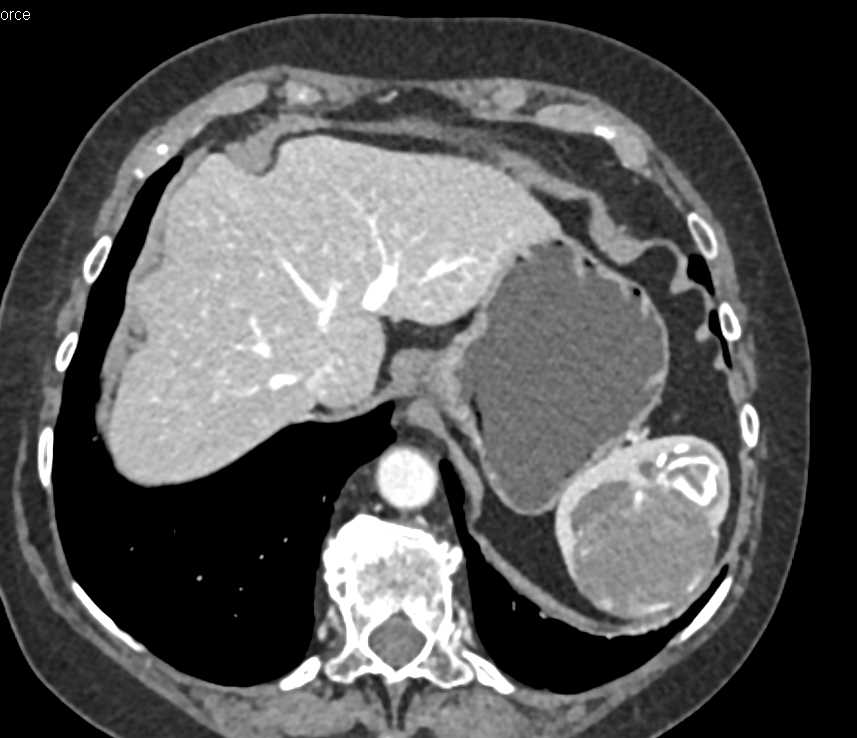

Cirrhosis with Splenomegaly and Large Varices